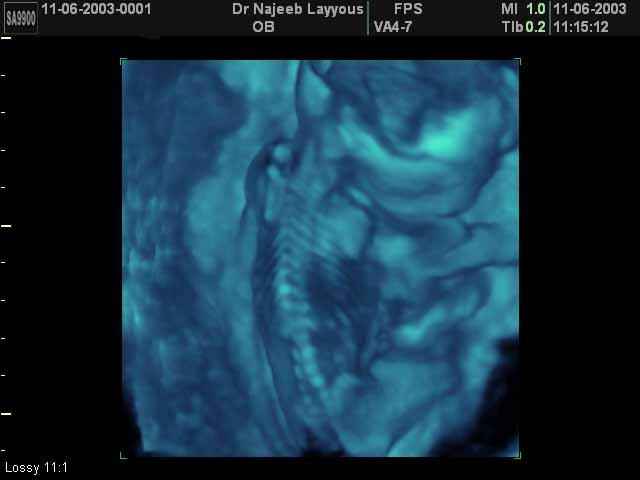

- 3D Photos échographie du squelette du fœtus

3D Photos échographie du squelette du fœtus | Dr N Layyous